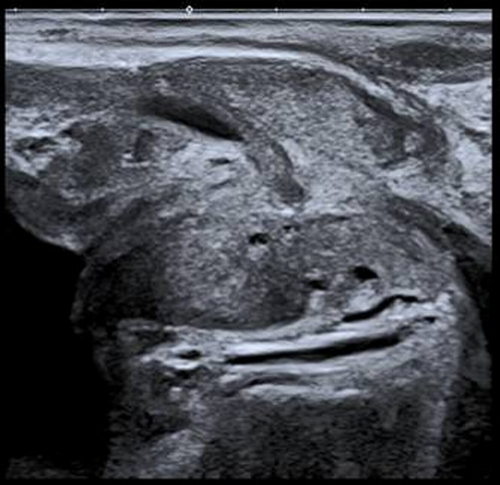

自临床使用以来,检查医生都反应二维图像很清晰,特别是一些新增功能,更受欢迎。1.彩超血流技术除常规CDFI、高级动态血流技术外,还具备超微细血流技术,能检测极低速血流(流速0.1-0.4cm/s),而微细低速血流广泛存在于各类疾病病灶的滋养血流、新生血流,能快速、便捷的帮助超声医生对疾病的准确诊断和鉴别诊断。2.声衰减成像功能,可对肝脏组织的衰减系数进行测量及可视化显示,可以对脂肪肝作出量化诊断,是诊断脂肪肝的有效定量工具。早期发现和量化评估肝脂肪变性,利于及时处理,防止病程进展。3.双平面探头(凸阵+线阵),为前列腺穿刺、肛周脓肿、阴道尿道、盆底功能障碍等疾病的诊断治疗提供不可替代的优势。凸、线双平面探头在前列腺、肛周穿刺活检中,实时快捷观察冠状面、矢状面,确定穿刺针路径、位置,提高穿刺活检成功率。4.浅表微小钙化增强显示技术,显著提升0.1-0.2mm微钙化点的检测识别能力。可以与原始图像实时双幅对比显示,可应用在乳腺、甲状腺等腺体组织恶性肿瘤的早期筛查。5.术中探头,配置穿刺引导架、能提高肝、肾等腹腔脏器的穿刺准确率。